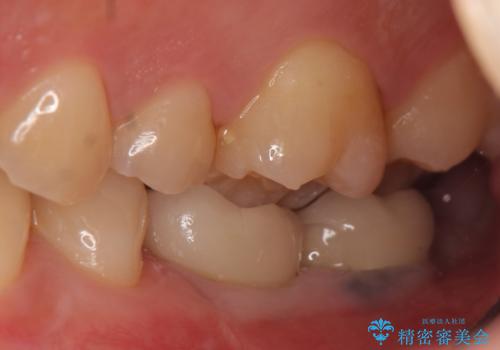

- 数年前に左下の奥歯を2本失ってから物が咬めないため何とかして欲しいと当院にいらっしゃった方の症例です。

左下にインプラント(ストローマン)を2本埋入し、オールセラミッククラウンによる補綴を行いました。

今回用いたオールセラミッククラウンはジルコニアフレームという白い素材の上にセラミックを盛っているため、審美性が非常に高いのが特徴です。

また、ジルコニアは人工ダイヤモンドの材料にも使われているほど高い強度を持っており、そのためオールセラミッククラウンは審美性だけでなく、奥歯やブリッジの補綴も可能とするクラウンです。